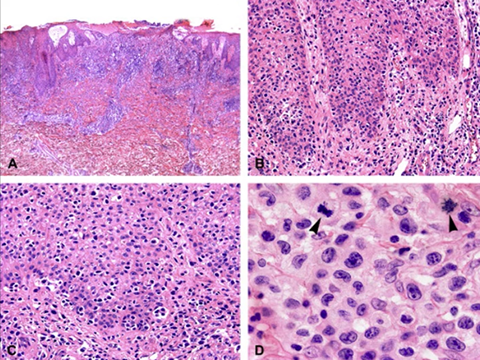

Cutaneous lymphoid hyperplasia in a 72-year-old man who presented with several purple-brown plaques on his cheeks and temples. A, The nodular infiltrate extends through the dermis with sparring of the overlying epidermis. B, It is characterized by scattered follicles with well-defined, reactive-appearing germinal centers, some of which have surrounding mantle zones. Many CD20-positive B cells are in the reactive follicles (C), and more numerous CD3-positive small T cells are present in the interfollicular areas (D). B-cell clonality studies (not shown) were negative for a clonal IGH or IGK gene rearrangement. [19]